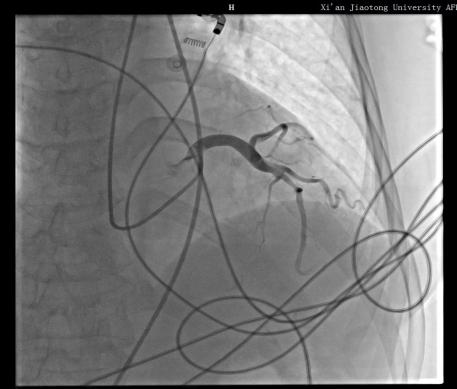

告知患者及家属全脑血管造影及冠脉造影相关手术风险后,家属表示理解并签字同意全脑血管造影及冠脉造影术。手术如期进行,在神经内科导管室为患者实施了“经股动脉行全脑血管造影术+冠状动脉造影术”。手术历时1小时05分,科室之间配合默契,顺利完成此次手术。

此项技术是在脑血管造影基础上同时进行心血管造影,一次穿刺就可以检查“脑”血管和“心”血管,将原本需要两次才能完成的检查一次性完成,不仅减少了患者反复动脉穿刺的痛苦,也极大地缩短了检查时间,降低了检查及治疗费用。此次多学科联合诊疗,制定脑心血管同时造影,为患者寻找出了病因,共同为患者的生命健康保驾护航!